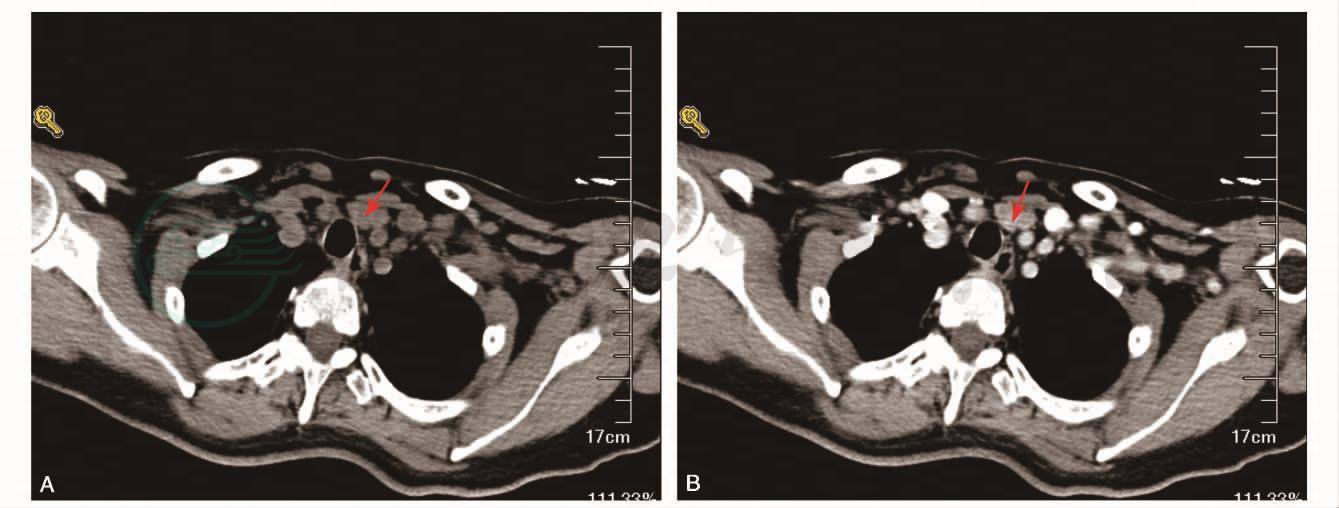

血、尿常规、肝功能、肾功能、血糖均正常,血清钾离子4.2mmol/L,血清钠离子145mmol/L,血清氯离子98mmol/L。碱性磷酸酶(ALP)360U/L(正常值40~150U/L)。血清钙离子5.5mmol/L(正常值2.1~2.55mmol/L),血磷0.56mmol/L(正常值0.9~1.6mmol/L)。血甲状旁腺激素(PTH):701pg/ml(正常值14~72pg/ml)。腹部超声:胆囊多发息肉。甲状腺彩超:甲状腺多发结节,左锁骨上窝结节,大小1.9cm×1.8cm×1.0cm,边界清,低回声;颈部增强CT:左侧甲状腺腺体后下方、气管左前方不规则结节影,2.0cm×1.1cm,增强后结节中等强化;考虑甲状旁腺腺瘤(图1)。

图1 颈部增强CT箭头所示左侧甲状腺腺体后下方、气管左前方不规则结节影,大小2.0cm×1.1cm,增强后结节中等强化